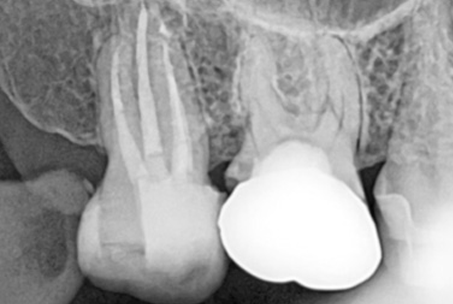

The images above show actual cases treated at SMILE FACE DENTAL CLINIC.

To a non-specialist, they may appear to be ordinary X-rays, but dentists can instantly recognize them.

They can appreciate both the complexity of the treatment and the care and precision involved.